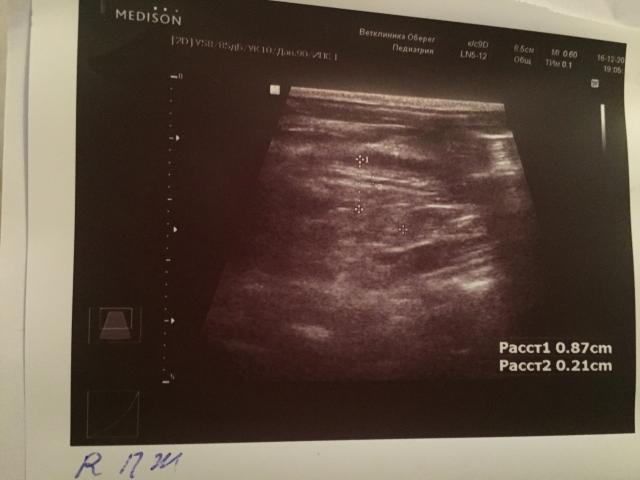

Если можно, то немного подробнее. На основании чего вам поставили такой диагноз, только на основании проведенного УЗИ? Может быть, собаке брали какие-то анализы? Если да, то выложите, пожалуйста, здесь их результаты. Если только данные УЗИ, то это разговор ни о чем (я имею ввиду панкреатит). Гастрит по данным УЗИ вообще не ставят.

К сожалению, ничего не могу рассмотреть. Попробуйте сами прочесть описание с фото. Если сможете, сделайте снимок более качественным. Или можно снять крупнее по частям. Может быть, тогда буквы будут видны более четко.

Спасибо, фотографии четкие. Я все прочитал. Как я и думал, там и "не пахнет" никаким гастродуоденитом, а тем более, панкреатитом.